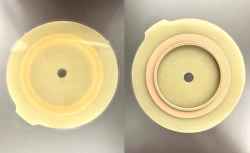

Medical product is intended for use in colostomies, ileostomies and urostomies for hermetic and secure attachment of stoma bags to the skin of the anterior abdominal wall, as well as to protect the skin of the peristomal area from stoma secretions and preserve the physiological functions of the skin due to the absorption of natural skin moisture (sweat, sebum).